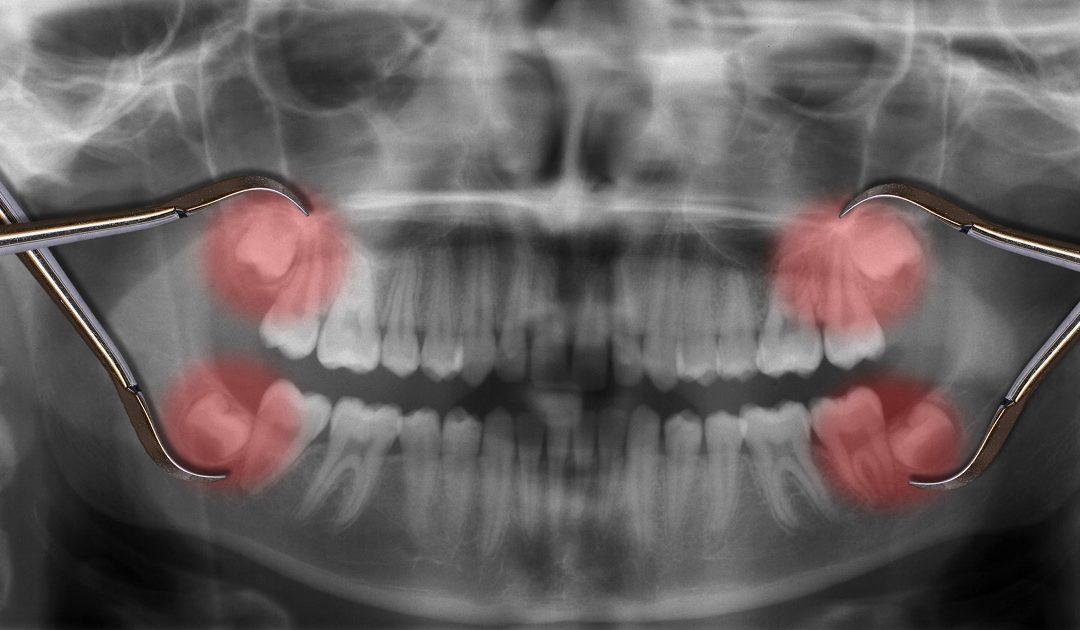

with 3D facial scanning, digital impressions and same-day solutions.

- We use high-tech tools that make appointments faster and more accurate